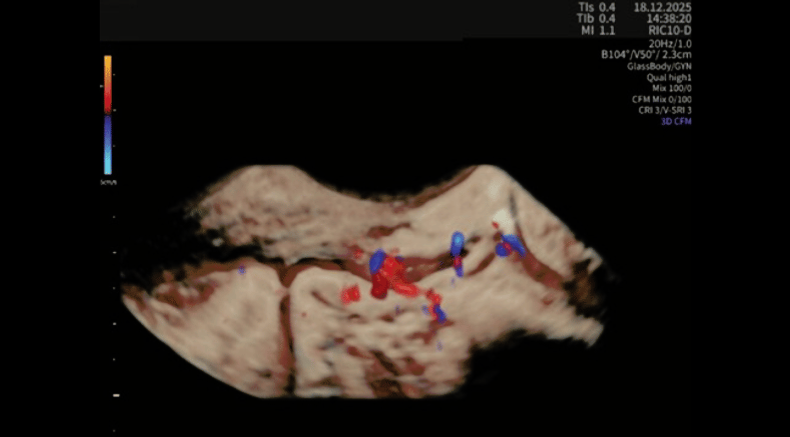

HDlive GlassBody 3D rendering with integrated color Doppler flow mapping, showing hypoechogenic nodule with marked intralesional vascularity

Barra, F., Maramai, M., Olcese, F., Beleva, D., Gustavino, C. and Ferrero, S. (2026), Decidualized posterior compartment deep endometriosis: three-dimensional rendering and Doppler-based vascular assessment. Ultrasound Obstet Gynecol. https://doi.org/10.1002/uog.70225